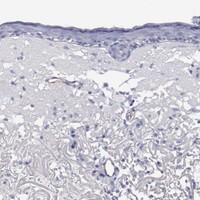

Enhanced - Orthogonal

Antibody staining mainly consistent with RNA expression data across 43 tissues.

LOW EXPRESSION

Skin 1

RNA expression: 38.5 nTPM